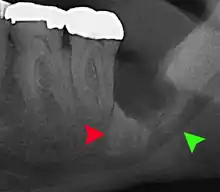

| 3D CT of an impacted wisdom tooth adjacent the inferior alveolar nerve prior to removal of wisdom tooth | |

Long-term complications can include periodontal complications such as bone loss on the second molar following wisdom teeth removal. Bone loss as a complication after wisdom teeth removal is uncommon in the young but present in 43% of those of 25 years of age or older.[22] Injury to the inferior alveolar nerve resulting in numbness or partial numbness of the lower lip and chin has reported rates that vary widely from 0.04% to 5%.[22] The largest study is from a survey of 535 oral and maxillofacial surgeons in California, where a rate of 1:2,500 was reported.[25]

Coronectomy

Coronectomy is a procedure where the crown of the impacted wisdom tooth is removed, but the roots are intentionally left in place. It is indicated when there is no disease of the dental pulp or infection around the crown of the tooth, and there is a high risk of inferior alveolar nerve injury.[31]